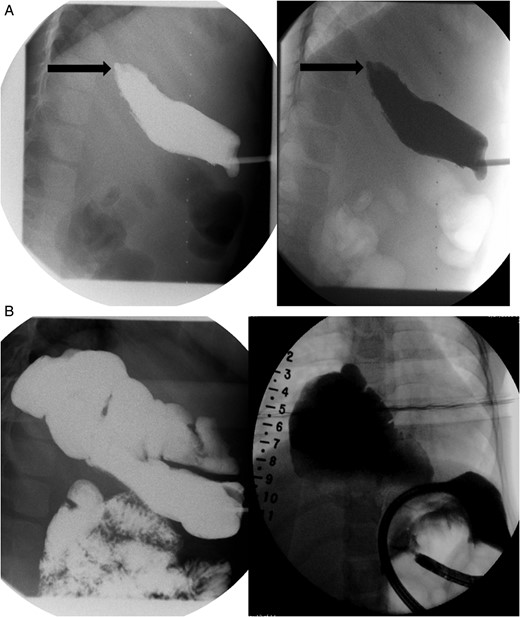

With the distal colon graft in place, as well as the distal esophageal segment, we recommended a combined procedure with graft removal and growth induction given the 8.2-cm gap (Fig. 1A and B). A thoracoabdominal incision was made and the colonic conduit was dissected away from the diaphragm; extensively mobilized from the left lateral segment of the liver and lung; and, transected from its anastomosis with the stomach. The stomach was then repaired in two layers. Traction sutures, using 4.0 prolene sutures, were then placed in the muscular layer of the distal esophageal segment and brought out onto the chest wall.

(A) Lateral view during her initial fluoroscopic examination illustrating a small, distal (lower) esophageal remnant present in situ (Black arrows). Contrast was injected through her existing gastrostomy tube. (B) Anterior–posterior (AP) view during initial fluoroscopic examination illustrating an aperistaltic, native colonic interposition in situ with significant dilatation.